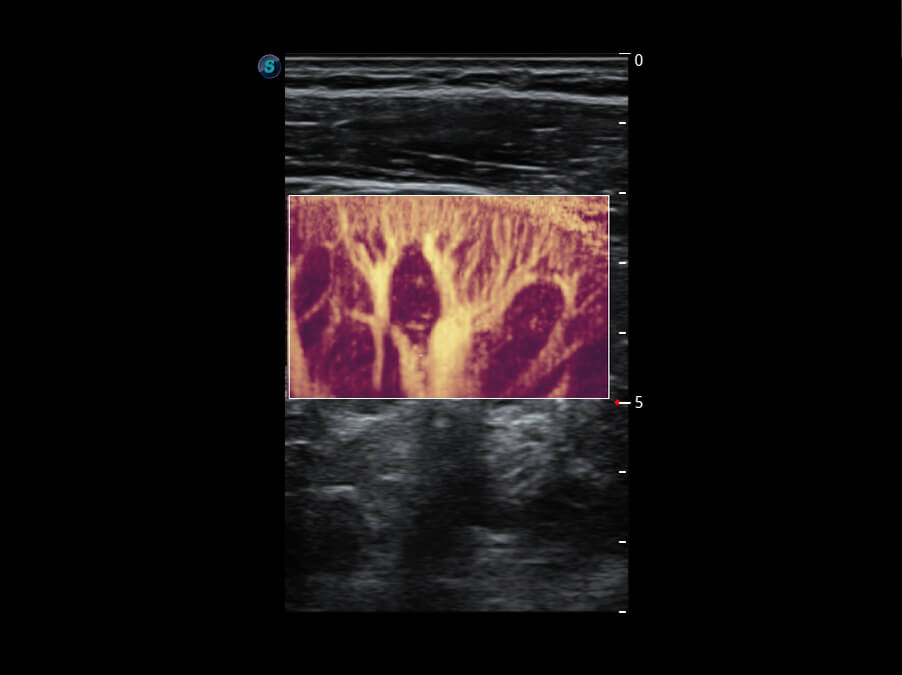

性能优异的硬件架构,极大提升超声系统的运行效率和数据处理能力。相比以往超声成像系统,Wis+平台为您带来极快的响应速度和成像帧频,提升检查流畅度。

S60探头工艺,从前端信号处理每一个环节采集无损声学数据,真实还原组织原貌,再现解剖细节。